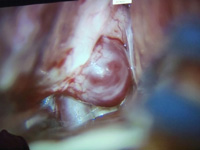

Aneurisma gigante paraclinoideo.